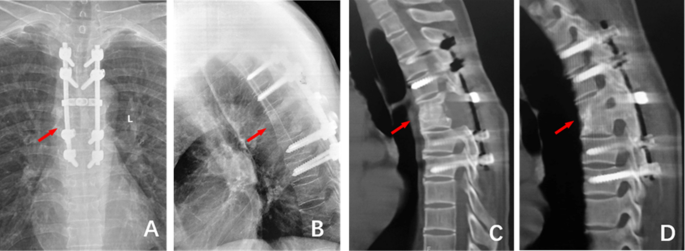

5 years after the operation, (A)and (B) The frontal and lateral X-ray films showed good internal fixation position, bone graft fusion, and Cobb Angle of 20°; (C) and (D): CT examination showed good internal fixation position and bone graft fusion.